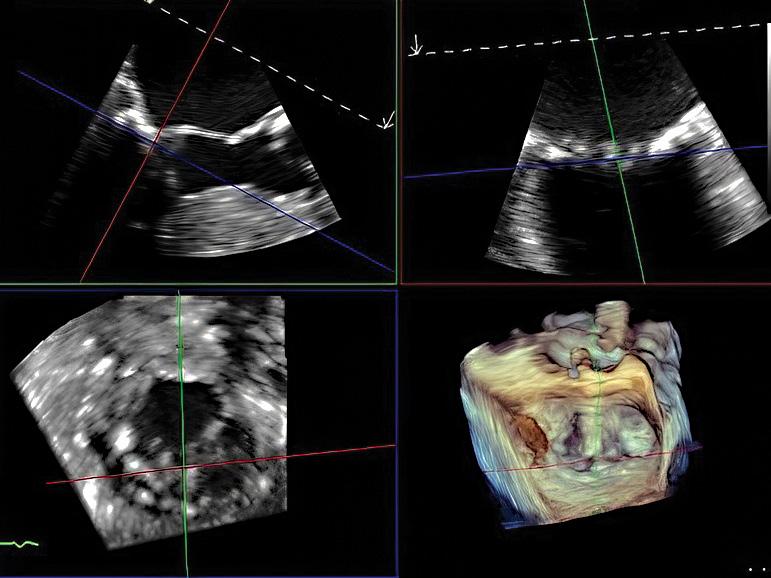

Transesophageal echocardiography showing 3-dimensional multiplane reconstruction of the mitral valve with HCM.

not provide the necessary information or there is a contraindication. Cardiac computer tomography (CT) can define cardiac anatomy (including detecting a myocardial bridge often present with HCM) but provides limited myocardial tissue characterization. Coronary CT angiography is often used in preoperative planning of young HCM patients undergoing surgical septal reduction therapy. Transesophageal echocardiography is utilized intraoperatively to guide septal myectomy.

Otherwise, it is occasionally also used when there are unresolved concerns for alternative mechanisms of LVOTO or to better characterize the mechanism of mitral regurgitation.